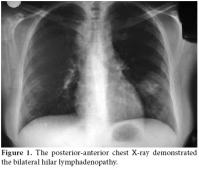

The laboratory testing results were as follows: rheumatoid factor (RF), 11 U/ml (0-20); erythrocyte sedimentation rate (ESR), 67 mm/h (0-20); C-reactive protein (CRP), 85.43 mg/dl (0-5); and the total blood count, urea, creatinine, and electrolyte values were normal. The hepatitis, antinuclear antibody (ANA) along with the Salmonella and Brucella titers were all negative. The purified protein derivative (PPD) skin and pathergy tests were also negative. No findings were detected on the throat culture or in the direct fecal and parasite examinations. HLA-B27 was negative. A chest X-ray showed the hilar plenitude (figure 1). High resolution computed tomography (HRCT) revealed the bilateral hilar lymphadenopathy (LAP) and multiple mediastinal LAP along with several nodules adjacent to several irregular nodules (the largest was 2.5x1.5 cm) in both lungs, which was compatible with stage II sarcoidosis (figure 2). Using a gallium-67 whole body screening method, an activity enhancement in both the hilar and mediastinal regions was consistent with lymph node involvement. The diagnosis of sarcoidosis was confirmed by a bronchoscopic biopsy. A pelvis radiograph and sacroiliac magnetic resonance imaging (MRI) were performed, and the results were normal. The patient was diagnosed as having Löfgren's syndrome, which is a clinical subtype of acute sarcoidosis involving acute arthritis, LAP, and EN. Steroid treatment was administered, and recovery was observed on the arthritis of the right ankle and EN after two weeks. On follow-up, the clinical and laboratory findings (ESR, 35 mm/h; CRP, 7.89 mg/dl) had improved dramatically. During the clinic management of the patient at three months, the patient complained about hip pain, so a radiograph of the sacroiliac joint was performed again. Sclerosis was shown in the inferior regions of both sacroiliac joints on the sacroiliac X-ray (figure 3), and right sacroiliitis was found on the MRI of the sacroiliac joints (figure 4). The complaints of the patient were address by administering nonsteroidal antiinflammatory drugs (NSAIDs), and the patient continued to be followed up.